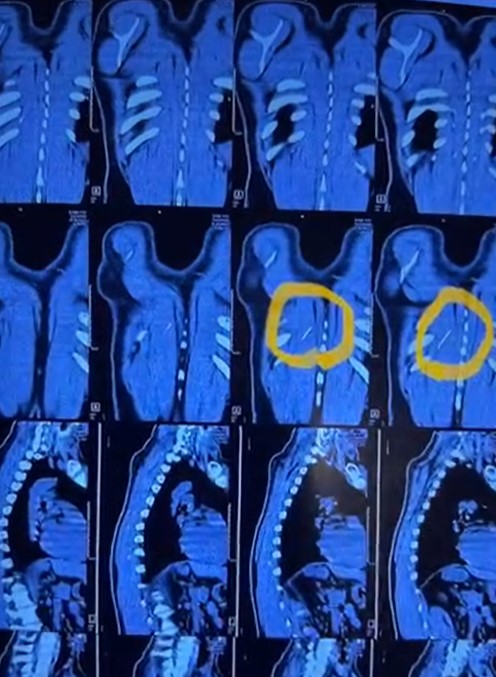

قام المريض بالتوجه إلى مستشفى بنها الجامعي وقام أطباء المستشفى بإجراء الأشعة اللازمة للكشف عن المريض وتبين بالفحوصات والأشعة وجود إبره تنجيد طولية خلف القفص الصدري تم حجز المريض وتقديم كافة الخدمات الطبية.

ونجح فريق من قسم جراحة القلب بمستشفى بنها الجامعي بقيادة الدكتور محمد الجزار من استخراج الإبرة وتبين أنها تقطعت إلى قطع بها صدأ، حيث استمرت بداخل ظهر المريض لأكثر من عامين.